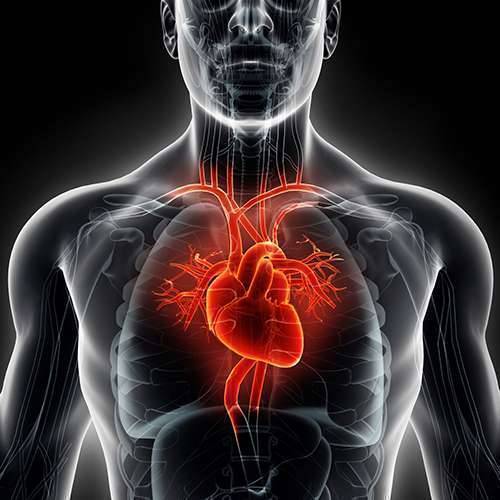

قصور القلب هو حالة تقدمية مزمنة تؤثر على قوة ضخ عضلات القلب. في حين يشار إليها في كثير من الأحيان باسم “قصور القلب”، يشير على وجه التحديد إلى المرحلة التي يتراكم فيها السائل حول القلب ويؤدي إلى ضخه بشكل غير فعال.

لديك أربع غرف القلب. يحتوي النصف العلوي من قلبك على اثنين من الأذينين، والنصف السفلي من قلبك به بطينان. تضخ البطينات الدم إلى أعضاء وأنسجة الجسم، وتستقبل الأذينين الدم من جسمك أثناء دورانه من بقية أجزاء الجسم.

في حالة فشل القلب، قد تصبح غرف الضخ الرئيسية في قلبك (البطينين) صلبة ولا تملأ بشكل صحيح بين النبضات. في بعض حالات قصور القلب قد تتضرر عضلة القلب وتضعف، وتمتد البطينات (تتوسع) إلى درجة أن القلب لا يستطيع ضخ الدم بكفاءة في جميع أنحاء الجسم.

يمكن أن يشمل قصور القلب الجانب الأيسر (البطين الأيسر)، الجانب الأيمن (البطين الأيمن) أو كلا جانبي قلبك. بشكل عام يبدأ قصور القلب بالجانب الأيسر، وبالتحديد البطين الأيسر – غرفة الضخ الرئيسية في قلبك.